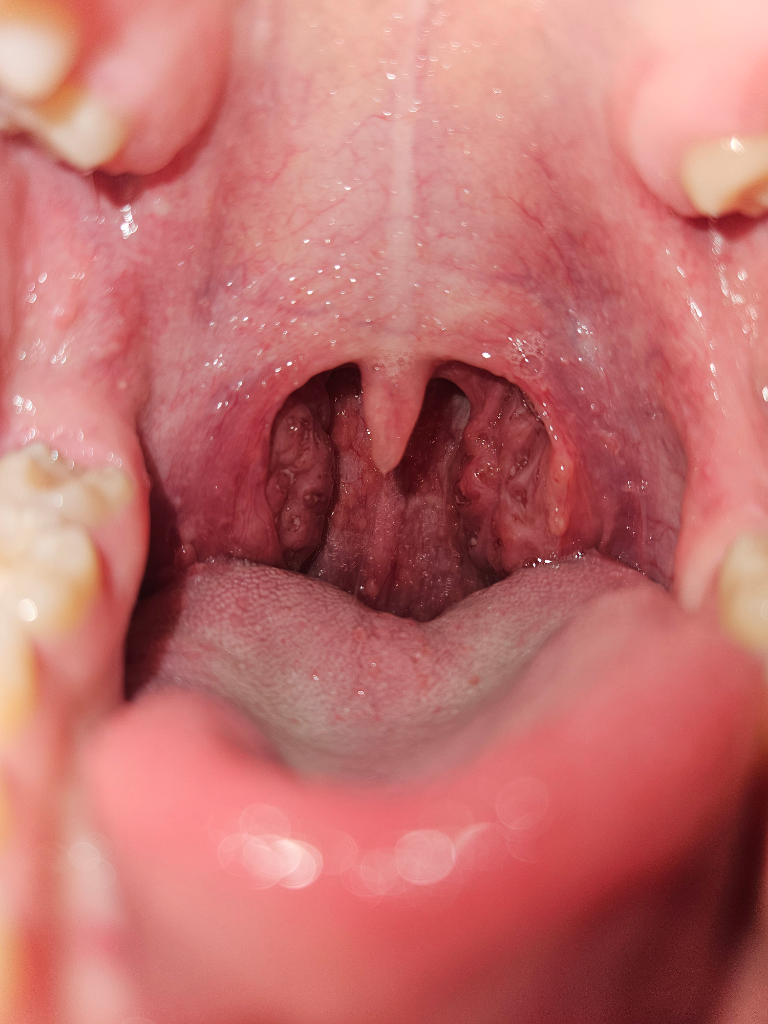

편도염은 편도 주위에 염증이 생기는 것을 말하며, 세균성과 바이러스성 두 가지 유형으로 나뉩니다. 세균성 편도염의 경우, 주로 A군 베타-헤모릴리틱 연쇄상구균이 원인균으로 알려져 있으며, 다음과 같은 증상들이 나타날 수 있습니다:

편도에 고름 또는 백색 점막의 침착